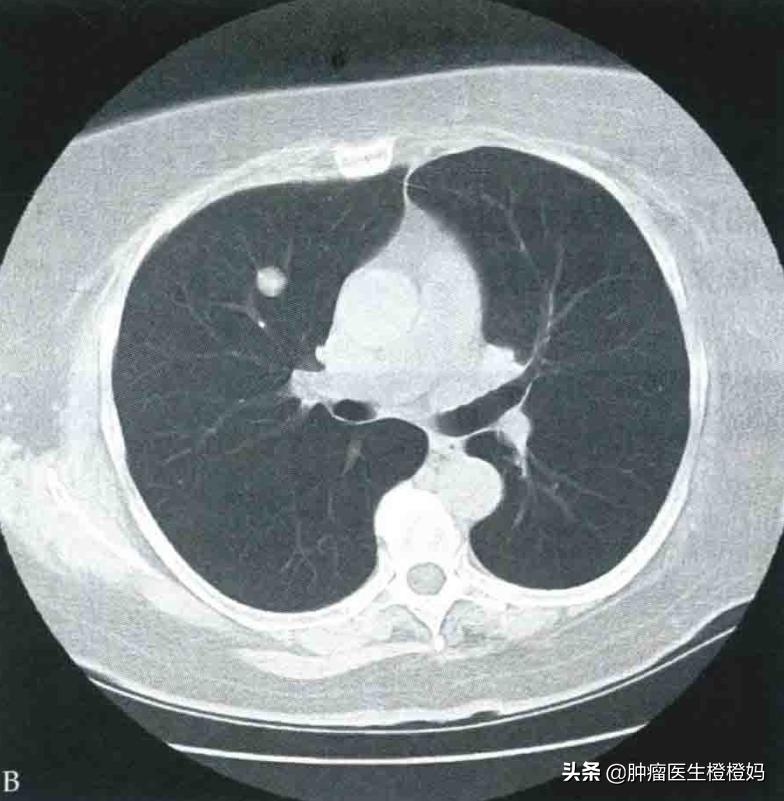

(3)肺转移

- 大部分肺转移患者是没有症状的,只有少数患者,大概占15%左右,会有咳嗽、胸痛或咯血等表现。咳嗽一般为干咳,多为刺激支气管时引起。当转移瘤侵犯支气管粘膜表面的微小血管时,可能会有咯血或者痰中带血的情况出现,极少出现大咯血。当转移灶累及胸膜或者直接侵犯胸壁时,会有胸痛的情况出现,呼吸或者弯腰活动时胸痛会加重。

肺转移病灶